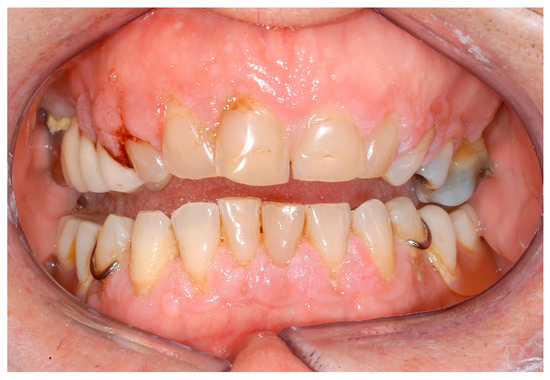

- Hanisch, M.; Jung, S.; Kleinheinz, J. Identification of rare diseases in the oral cavity. Internist 2018, 59, 972–980. [Google Scholar] [CrossRef] [PubMed]